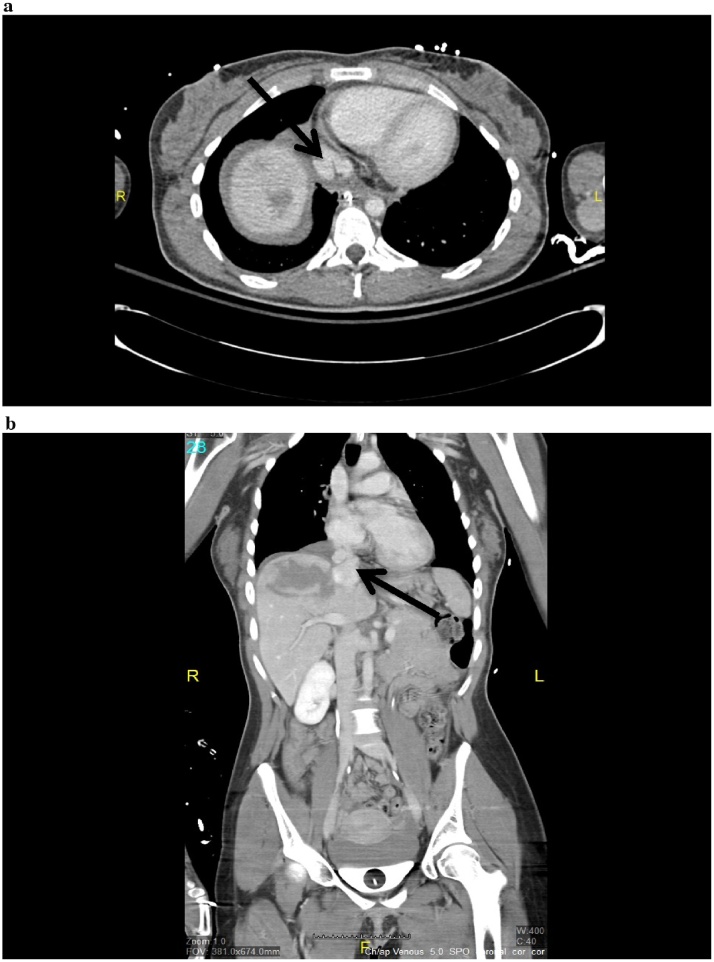

A 23-year-old woman presented to our level 1 trauma center after a head-on motor vehicle crash. The patient was in shock with a heart rate of 122 and a systolic blood pressure (SBP) of 92. A massive transfusion protocol was initiated. Patient received 4 units of packed red blood cells(PRBC) and her blood pressure stabilized. Focus abdominal sonographic test (FAST) was negative. With hemodynamic stability established a completion trauma computed tomography (CT) was performed. Injuries included grade IV liver laceration, grade I splenic laceration, unstable C2 fracture, right knee arthrotomy, left lower mid shaft femur fracture, left open distal tibia-fibula fracture, right posterior hip dislocation. Also revealed is an irregularity of the suprahepatic IVC with contained contrast extravasation consistent with an IVC pseudoaneurysm at the hepatic confluence of the IVC (Fig. 1). Observation of these lesions was felt to be the safest course of action in this severely injured polytrauma patient who, at the time of diagnosis, was hemodynamically stable. Her fluid management was closely monitored preoperatively using the end points of urine output, heart rate, and blood pressure. A central venous catheter was not initially placed due to concerns of further injury to the pseudoaneurysms. On hospital day 3(HD3) MRI of the brain indicated multiple punctate lesions consistent with fat emboli; subsequent TTE with bubble study found evidence of patent foramen ovale(PFO) with moderate right left shunting. On HD6, the patient was noted to be tachypneic; A CT angiogram of the chest was performed which showed a pulmonary embolism. Patient was placed on heparin drip. An IVC filter was also placed. Venogram performed at the time revealed no active extravasation.

Fig. 1.

a. An axial image from the patient’s initial computed tomography study demonstrates a pseudoaneurysm along the posterior aspect of the suprahepatic inferior vena cava (IVC). b. Coronal image demonstrates focal irregularity of the IVC at the confluence with the right hepatic vein.